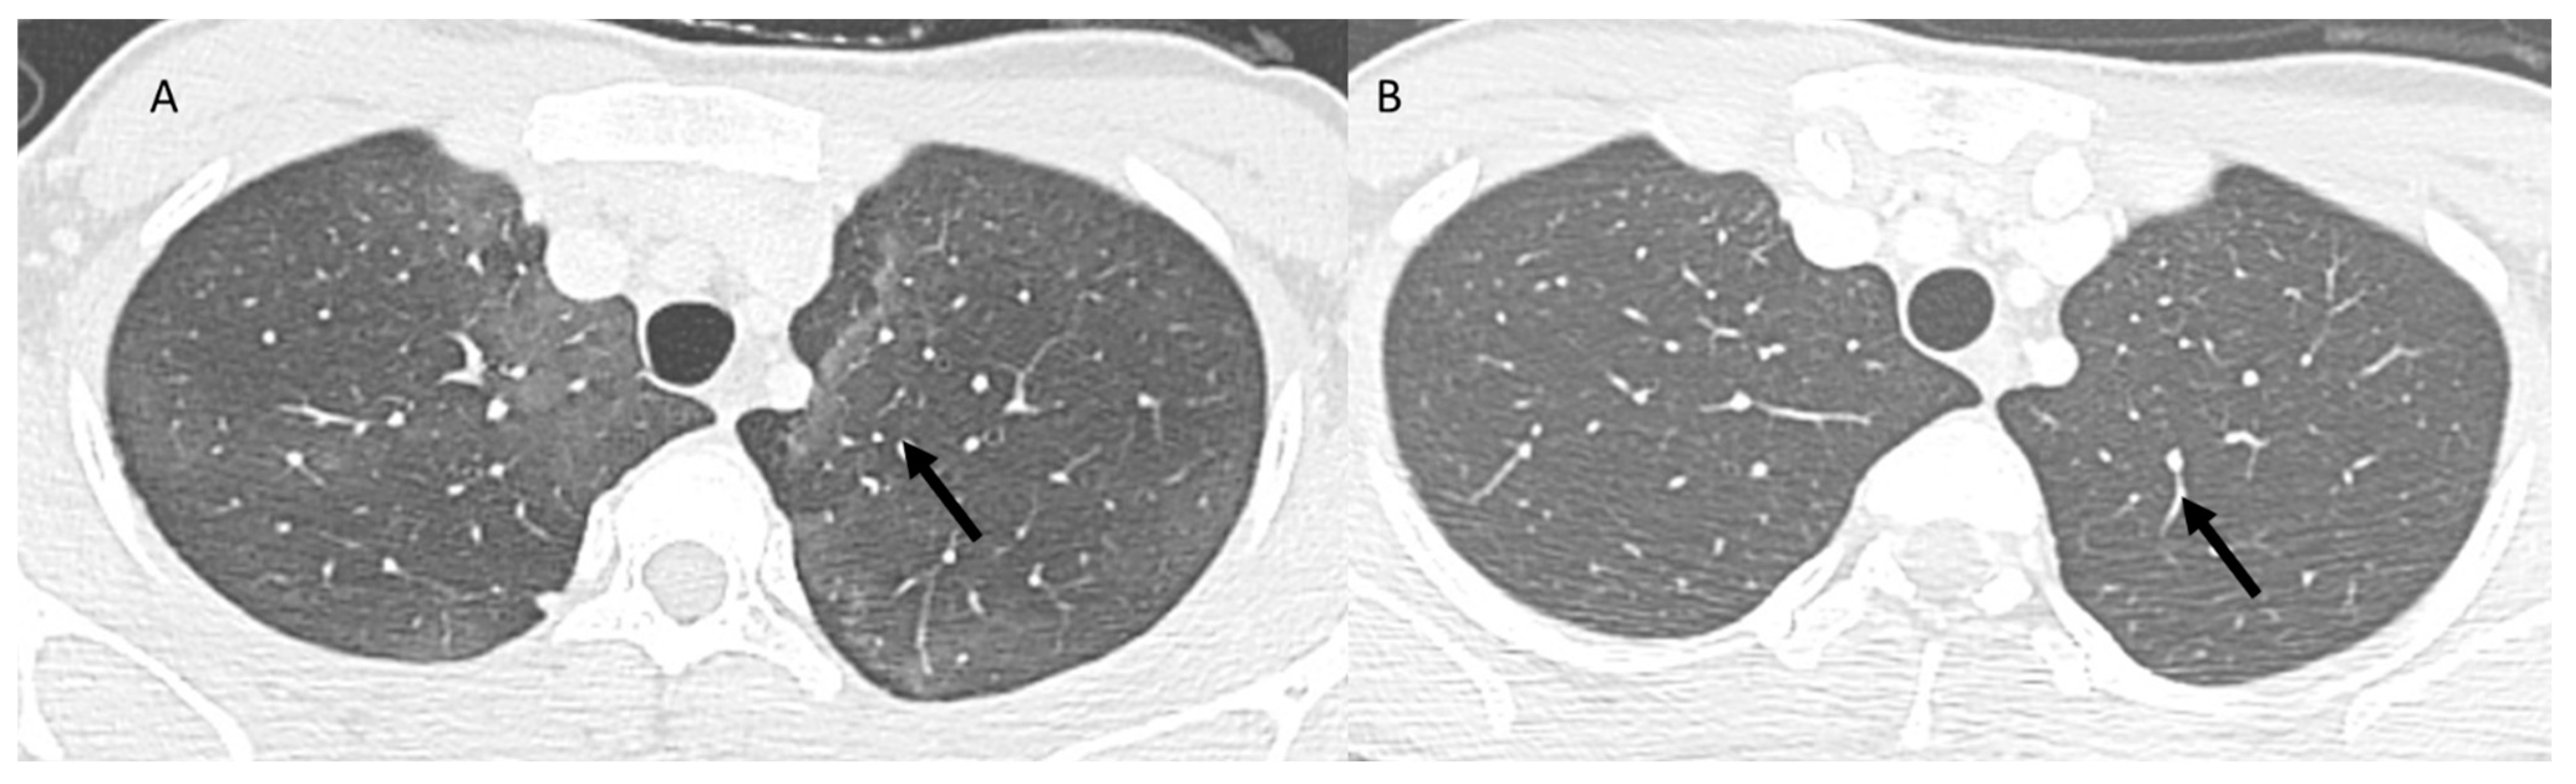

3.2. Immune-Related Pneumonia

| ICI-related pneumonitis | Diffuse (related to the phase of disease) | Ground-glass and reticular opacities; consolidative opacities; interlobular septal thickening; “crazy-paving” pattern | Autoimmune |